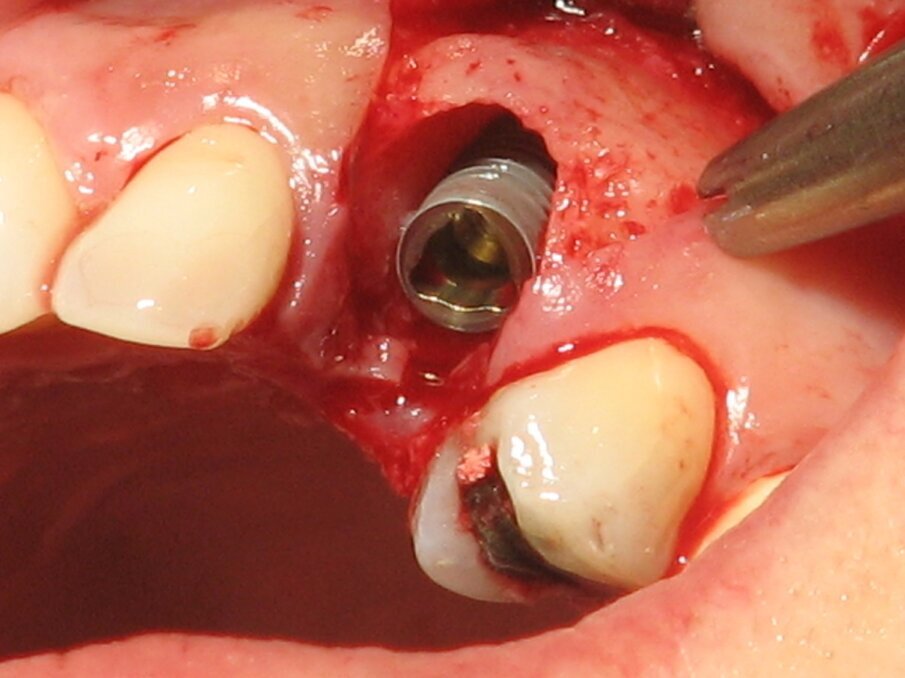

Imedijatna ugradnja implantata smanjuje broj hirurških intervencija i redukuje vreme potrebno da se izvede celokupni tretman. Idealno trodimenzionalno pozicioniranje implantata, očuvanje alveolarne kosti, sa posebnim akcentom na bukalnu koštanu lamelu, kao i zadovoljavajući izgled mekog tkiva mogu biti postignuti ovom procedurom. Mogu se očekivati visoki estetski rezultati.

Dugoročno preživljavanje implantata, i zdravlje tkiva koje ga okružuju, ne ispunjavaju zahteve koji se postavljaju pred savremenu implantologiju. Danas smatramo da je estetski učinak podjednako bitan za uspeh implantata. Ugradnja implantata i protetska rehabilitacija su posebno izazovne u esteskoj zoni. Detaljna analiza parametara neophodnih za idealno pozicioniranje implantata, kao što su dijagnoza, plan terapije, anatomski parametri, trodimenzionalno pozicioniranje, kao i dizajn implantata su od presudnog značaja za uspeh ove procedure.

U slučaju pravlinog odabira pacijenta, i pravilno postavljenje indikacije, imedijatna ugradnja predstavlja visoko uspešan modalitet lečenja sa procentom uspeha sličnom onom kod kasne ugradnje.